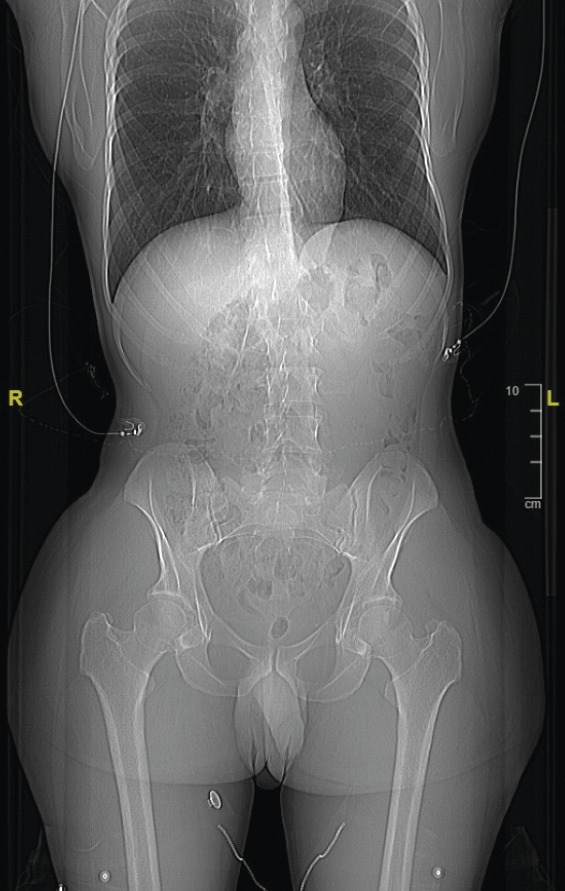

• Il mesure 1,91 m et pèse 92 kg. L’examen révèle une cyphose et une scoliose (fig. 1). Un prognathisme, une macroglossie, une hypertrophie des golfes frontaux, un élargissement des mains (fig. 2) et des pieds (il chausse du 47) ainsi que des sueurs nocturnes sont également constatés.